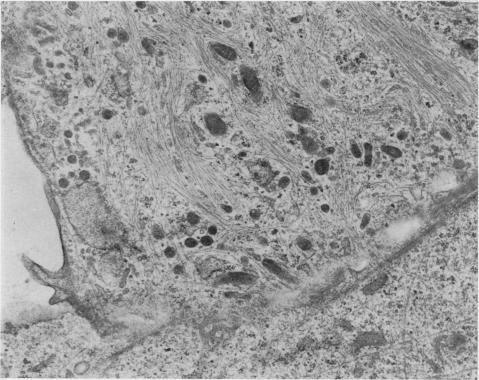

Cryostat sections and established in vitro cultures of dimethylnitrosamine(DMN)-induced renal mesenchymal tumours and monolayer cultures of transformed kidney cells derived from rats treated with a carcinogenic dose of DMN were examined by indirect immunofluorescence with human serum containing smooth muscle antibody. Eight mesenchymal tumours examined showed filamentous cytoplasmic staining of spindle cells infiltrating between renal tubules, whilst in normal kidneys interstitial cells were only weakly positive. In established in vitro cultures from 6 mesenchymal tumours, different patterns of staining were observed in morphologically different cell forms, ranging from fine filamentous staining in giant cells to diffuse cytoplasmic fluorescence in small bipolar cells, and cell outline staining in polygonal cells. In addition filamentous staining of microvillous projections and nucleolar staining were observed in some tumour cells. Monolayer cultures of transformed kidney cells showed strong staining of coarse, randomly-orientated cytoplasmic filaments, whilst fibroblasts cultured from normal rat kidney demonstrated an ordered array of fine, parallel filaments. Specificity of the immunofluorescent staining reaction was established by failure to obtain staining with normal serum, with smooth muscle antibody serum neutralized by homogenates of smooth muscle or extracts containing actin derived from smooth muscle. These results indicate that there is an apparent increase of actin-like contractile microfilaments in transformed cells and in renal mesenchymal tumours. The cytoplasmic contracile microfilaments in these cells may play a role in tumour cell mobility and invasion.

采用含平滑肌抗体的人血清通过间接免疫荧光法检测了二甲基亚硝胺(DMN)诱导的大鼠肾间充质肿瘤的低温切片和体外培养物,以及用致癌剂量的DMN处理的大鼠来源的转化肾细胞的单层培养物。所检测的8个间充质肿瘤显示,浸润于肾小管之间的梭形细胞的胞质呈丝状染色,而在正常肾脏中,间质细胞仅呈弱阳性。在来自6个间充质肿瘤的体外培养物中,在形态不同的细胞形态中观察到了不同的染色模式,从巨细胞中的细丝状染色到小双极细胞中的弥漫性胞质荧光,以及多角形细胞中的细胞轮廓染色。此外,在一些肿瘤细胞中还观察到微绒毛突起的丝状染色和核仁染色。转化肾细胞的单层培养物显示出粗大、随机排列的胞质细丝的强染色,而从正常大鼠肾脏培养的成纤维细胞则显示出排列有序的细平行细丝。通过用正常血清、被平滑肌匀浆或含平滑肌肌动蛋白提取物中和的平滑肌抗体血清未能获得染色,确定了免疫荧光染色反应的特异性。这些结果表明,在转化细胞和肾间充质肿瘤中,肌动蛋白样收缩微丝明显增加。这些细胞中的胞质收缩微丝可能在肿瘤细胞的迁移和侵袭中起作用。